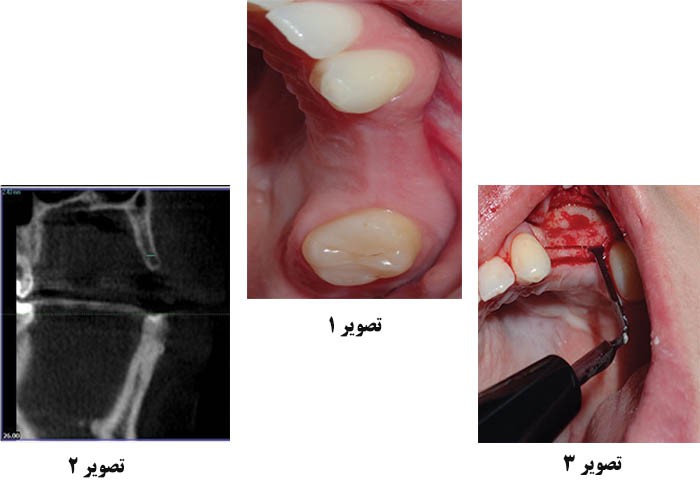

تصویر 1: وضعیت قبل از عمل بیمار، که در ناحیه ی عرض لبه ی ضعیف دندان آسیاب کوچک سمت راست و یک زیربرش کوچک در چهره دارند.

تصویر 2: تصویر ساژیتال از یک اسکن CBCT نشان دهنده ی لبه های نازک رسوب شده می باشد که در زمان مشاوره اولیه حدود 2.4 میلی متر بوده است.

تصویر 3: یک ابزار اره مانند برای ایجاد یک برش افقی در استخوان استفاده شد و لبه های باقی مانده را دو نیم کرد.

یک بیمار زن 40 ساله برای درمان دندان های از دست رفته در ناحیه دندان های شماره 12 و 13 اقدام کرده است (تصویر 1). دندان ها چند سال پیش پس از شکست درمان اندودنتیتی خارج شد. بیمار که به طور کلی سلامت دهانی خوبی داشت، از پوشیدن یک ابزار نصفه خسته شده بود و خواستار یک راه حل بلندمدت بهتری بود. از آنجاییکه پیوند حفره انجام نشده بود و دندان ها از چندین سال قبل از بین رفته بودند، رگه ها در ناحیه بی دندان به طور قابل توجهی جذب شدند. همچنين یک برش زیرین کوچکی نیز در صورت وجود دارد. معاینه داخل دهان و تجزیه و تحلیل CBCT نشان داد که اگر چه بین شکاف لبه و کف سینوس فضای زیادی وجود داشت، عرض لبه برای ایمپلنت فوری بدون شیارهای شکافتن ایمپلنت یا برآمدگی از طریق پوشش گونه کافی نبود (تصویر 2).

برای شروع عمل جراحی، یک ضربه ی محکم شکاف های نیمه حلقه ای و عمودی ایجاد می کند. تصویر کاملی از بخش های حلقه ای (تاجی) و لپی لبه ی جذب شده بدست می دهد. سپس یک سری برش برای تسهیل گسترش ریج به سمت صورت ایجاد شد. یک سیستم فراصوتی فیزوالکتریک (Osada ENAC OE-F15) و یک ابزار اره مانند برای برش استخوان تاج استفاده می شود، و در نهایت مرز رسوبی را در عمقی که مربوط به طول ایمپلنت برای پروسه انتخاب شده است، جدا می کند (تصویر 3).